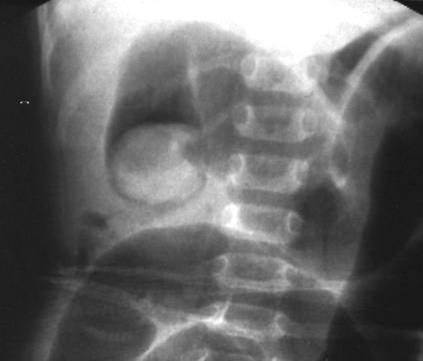

X線檢查:站立位*可見多個液氣平面及脹氣腸袢。